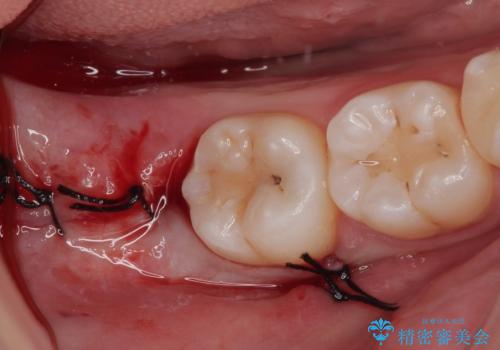

親知らずを抜きたい 親知らず抜歯

担当医 有澤哲郎